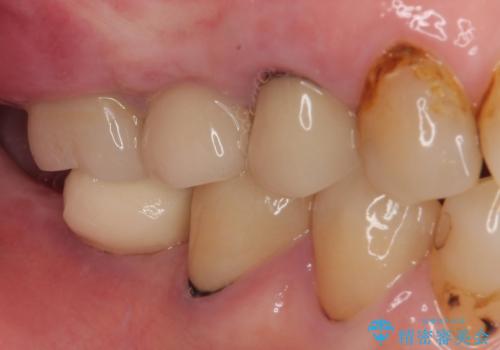

破折して抜歯となった奥歯 抜歯即時埋入・即時荷重インプラントによる補綴治療

歯肉を開いて確認をしたところ、著しく骨欠損しており、目視でも歯根破折が確認されました。

3つある歯根の内、1つのみに骨欠損がある状態で、インプラント埋入に十分な骨の状態でした。

抜歯即時埋入・即時荷重の適応と判断されたため、インプラントによる補綴治療を行うこととしました。

埋入時に十分な安定値が獲得でき、埋入した際に仮歯を装着することができました。

術後の経過は安定しており、抜歯から3ヶ月で治療を終えることができました。